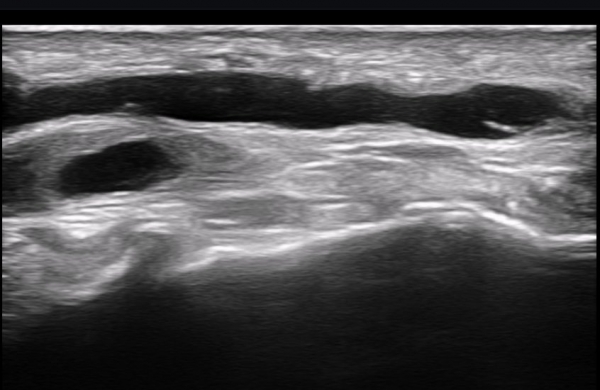

ÃÊÀ½ÆÄ ¼Ò°ß : ºñº¹½Å°æ Ⱦ´Ü¸é°Ë»ç¿¡¼­(»çÁø 1~13) ºñº¹½Å°æÀÇ Àú¿¡ÄÚ ºÎÁ¾°ú ´Üºñ°ñ°Ç³» ³¶Á¾¼º º´º¯ÀÌ °üÂûµÈ´Ù.